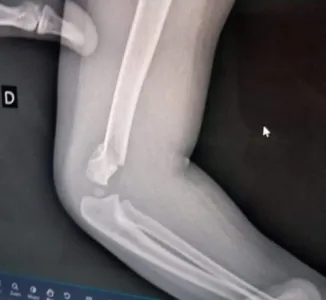

Bebê volta para casa com braço quebrado e família acusa professora

A criança passou por uma cirurgia de emergência e segue internada

Uma família de Pinhais, na Região Metropolitana de Curitiba, fez um boletim de ocorrência na quarta-feira (21) alegando agressão contra uma criança de um ano e meio no Centro Municipal de Educação Infantil Enedina Alves Marques.

Segundo com familiares, a agressão teria ocorrido na última terça (20), por volta das 15h30, mas a família só foi avisada às 17h15. Na agenda, de acordo com o boletim de ocorrência, estava escrito que ele estava machucado desde a hora do lanche, quando o bebê teria sofrido uma fratura no braço durante uma troca de fralda.

Em nota, a Secretaria Municipal de Educação de Pinhais afirmou que assim que soube do caso instaurou processo administrativo disciplinar e determinou afastamento cautelar da servidora durante a apuração da ocorrência. A secretaria afirmou ainda que “a criança foi rapidamente encaminhada ao atendimento de emergência e que a Administração está dando o suporte necessário à família”.

A criança passou por uma cirurgia de emergência no Hospital Evangélico Mackenzie na quarta (22), onde segue internada.

A polícia já investiga o caso.